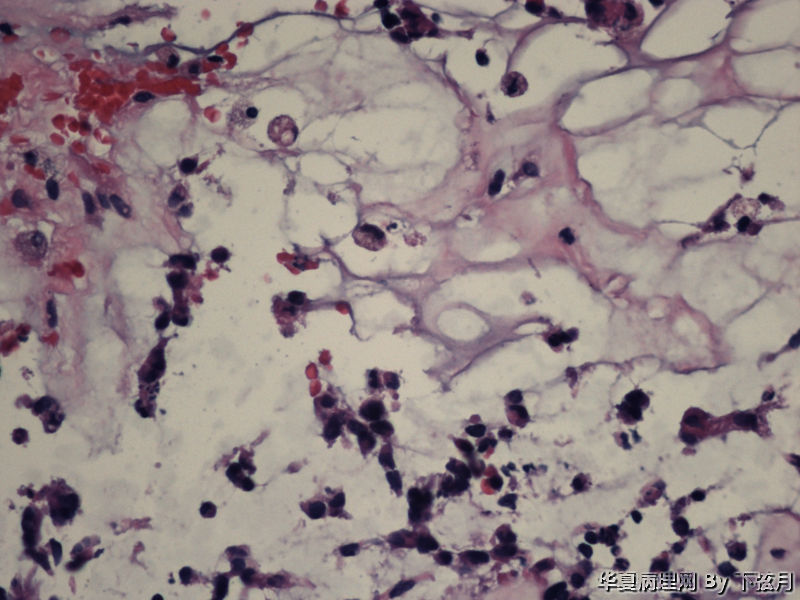

左侧颞叶及胼胝体膝部占位图8

描述:HE 400倍-3

This enhancing lesion with GFAP positive cells and should consider some type of glioma, probably high-grade.

But some cells in fig 7 and 8 are worrisome, need to rule out other type tumors, like chordoma. Other small round blue cell tumors.

考虑黏液型乳头状室管膜瘤

丰富黏液背景,漂浮乳头状或簇状分布的瘤细胞,免疫组化GFAP,S-100阳性。

有血管轴乳头,粘液样物中漂浮的细胞呈团块状和小乳头状。支持粘液型乳头状室管膜瘤。

EMA阴性,考虑脊索瘤样胶质瘤